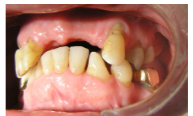

1) 1. Initial situation of teeth anterior and lateral view

2) Anterior view with denture

3. Presence of teeth

-UR7--- UR3UR2---UL3UL4UL5----

-LR7LR6--LR3LR2LR1LL1LL2LL3LL4--LR6--